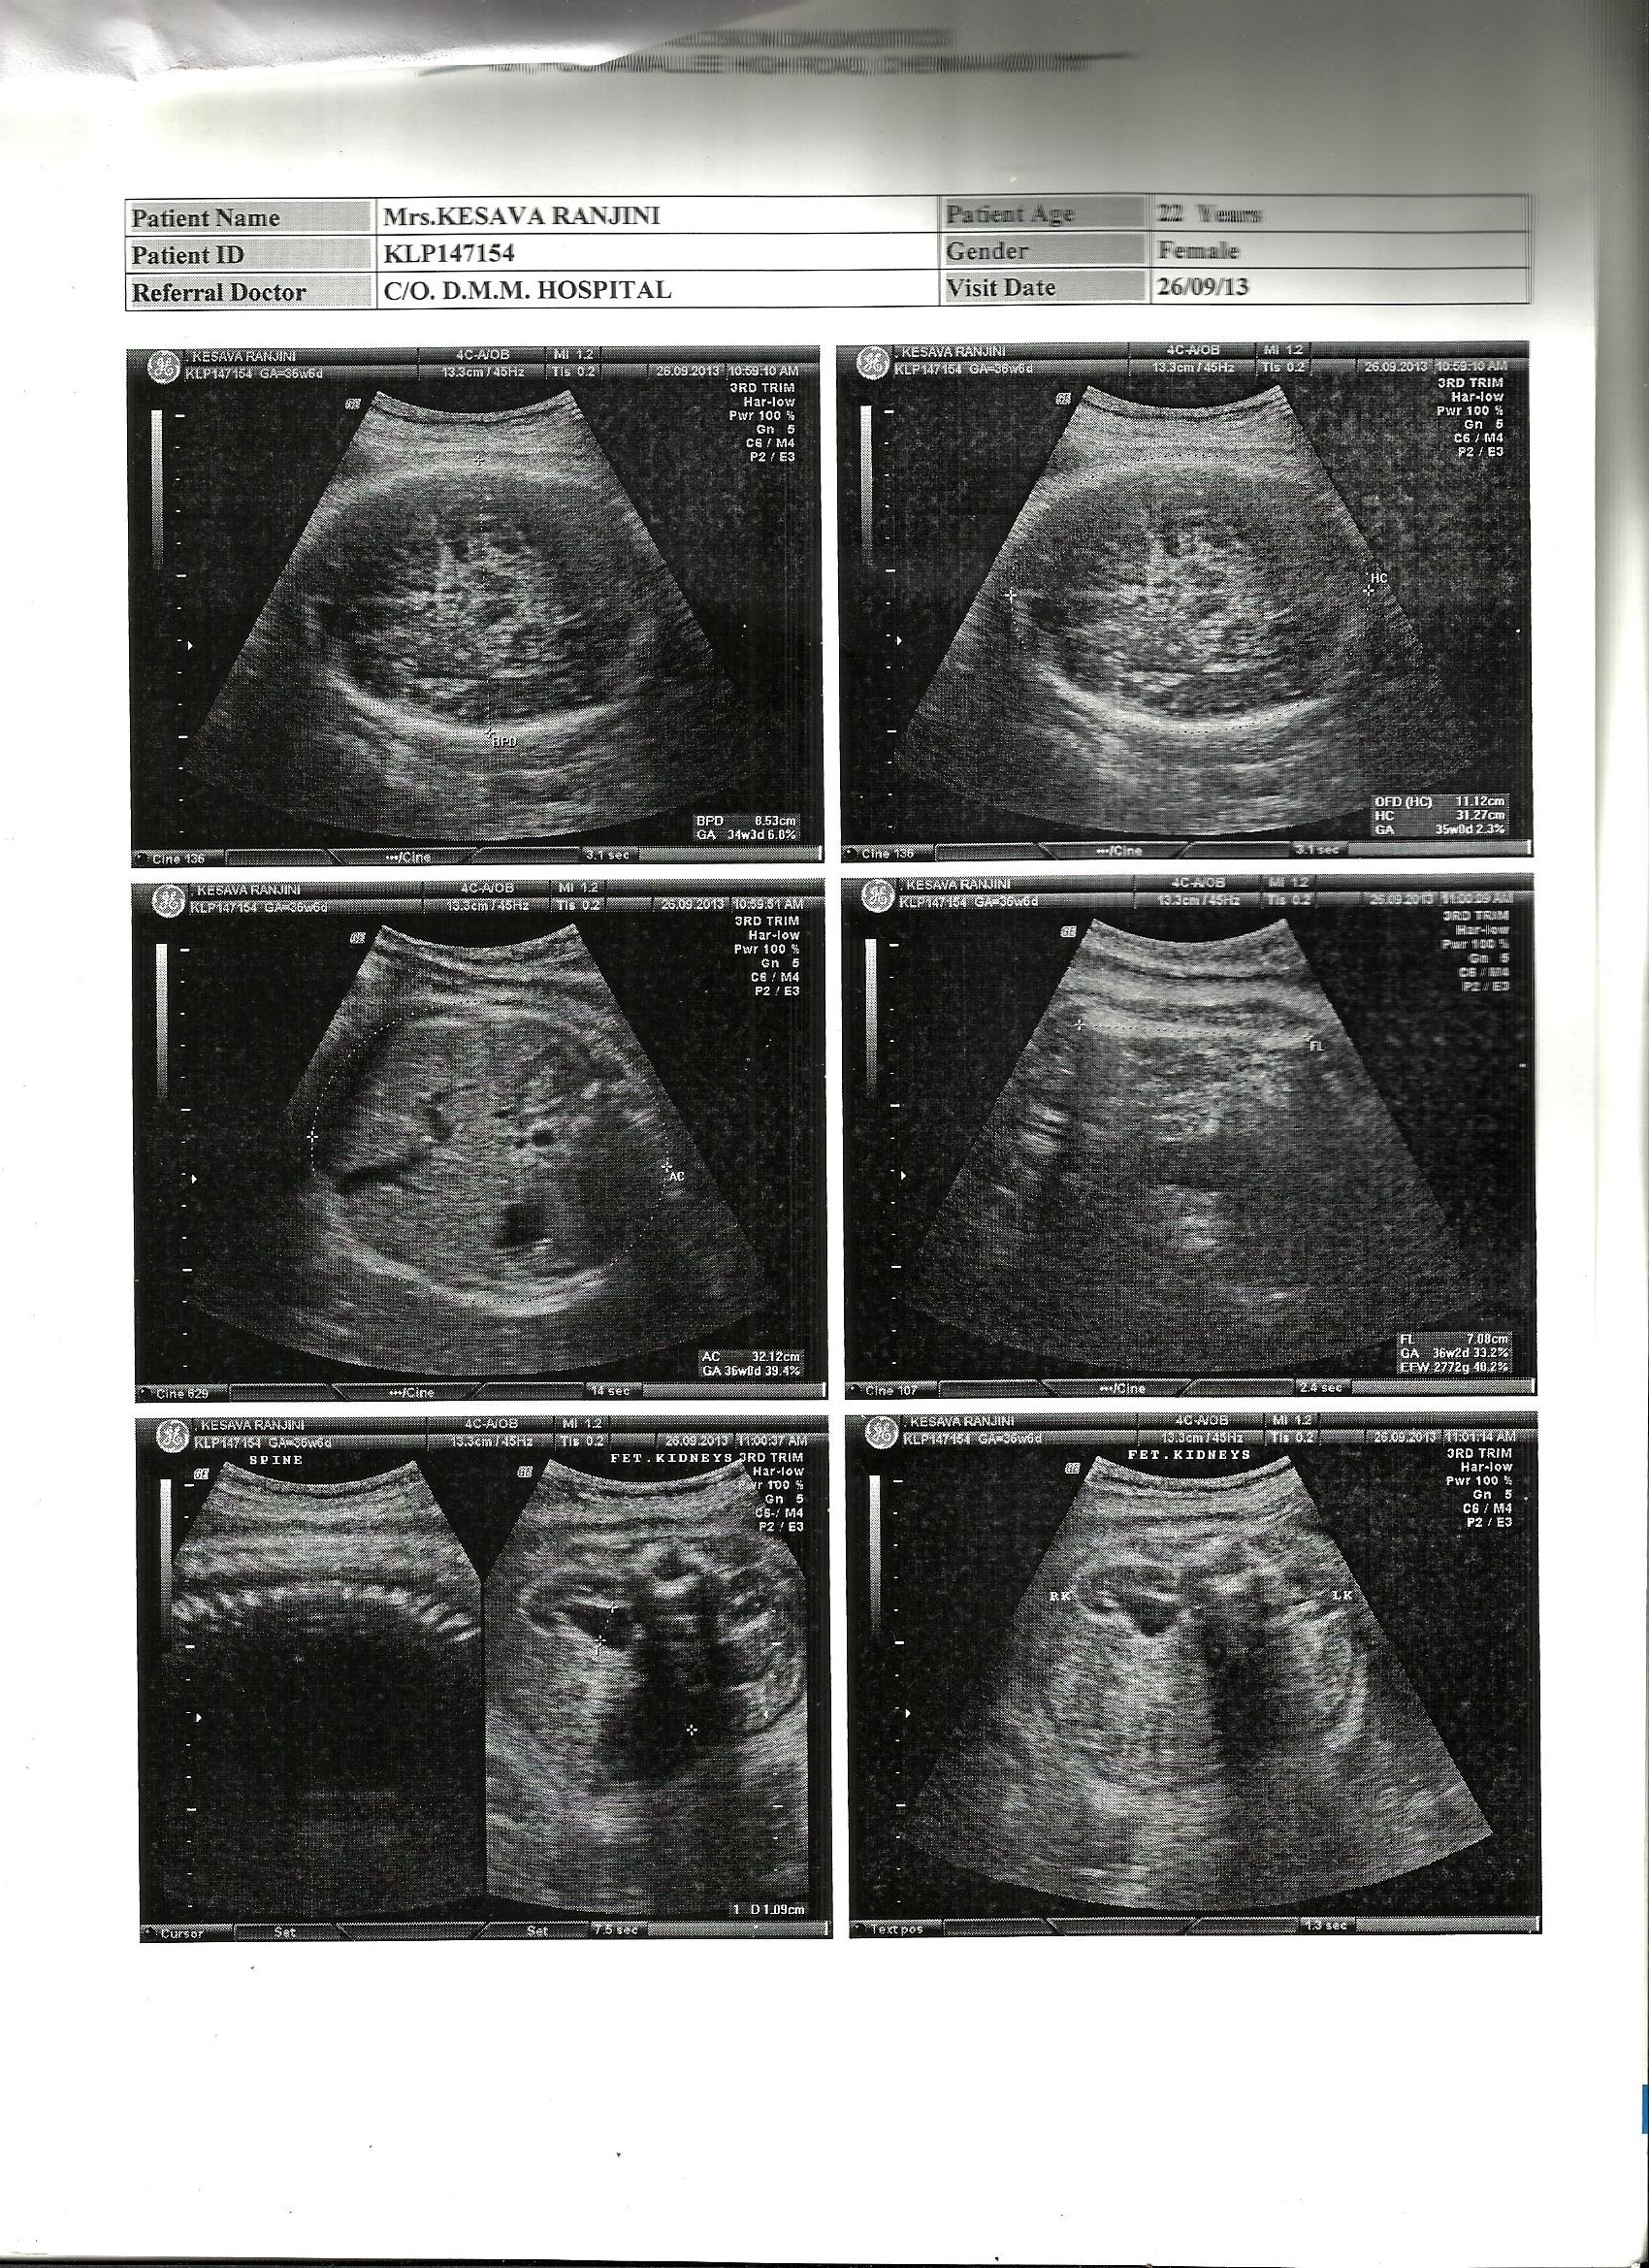

Yesterday the ninth month scan results came up!! posting the same for your guesses!!! Please post your guesses. Oct 18th is the due date. Feeling Excited!!!Attachment 14422Attachment 14423